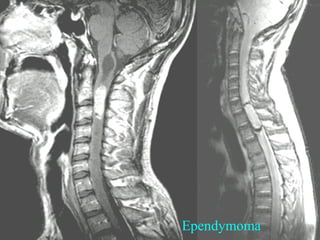

U MAØNG NAÕO THAÁT VAØ OÁNG

NOÄI TUYÛ (EPENDYMOMA)

a.Tæ leä : Thöôøng gaëp nhaát

b.Tuoåi vaø giôùi : 30-60, öu

theá nöõ .

c.Vò trí : Tuyû thaáp, choùp

tuyû, daây taän

d.MRI :

-Lôùn choùp tuyû, daây taän,

thöôøng nhieàu taàng, lan theo

oáng soáng.

-U bôø khoâng roõ, khoâng

ñeàu.

-Tín hieäu thaáp treân T1W,

cao khoâng ñoàng nhaát treân

T2W.

Ependymoma